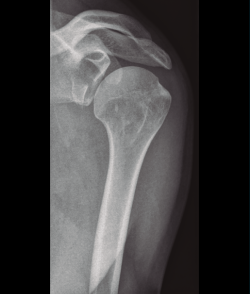

El húmero es el hueso más largo y de mayor tamaño del miembro superior. En el extremo proximal, se articula con la cavidad glenoidea de la escápula y forma la articulación glenohumeral. Según Court-Brown et al.(7), las fracturas del húmero proximal representan el 6% de todas las fracturas en adultos y en su estudio se revela que el 87% de estas fracturas fueron producidas por caídas. La mayoría de las fracturas proximales de húmero no están desplazadas; según la clasificación de las fracturas del húmero de Neer(8), cerca del 45% de todas las fracturas proximales del húmero son sin desplazamiento.

Shekelle et al.(9) concluyen que no existe evidencia en cuanto a la elección del tipo de tratamiento, pero sí resulta de gran importancia individualizar el tratamiento valorando de forma integral al paciente, considerando el grado de desplazamiento, la densidad ósea, la edad y las lesiones asociadas (Figura 5).

Figura 5. Radiografía simple de fractura del húmero proximal.